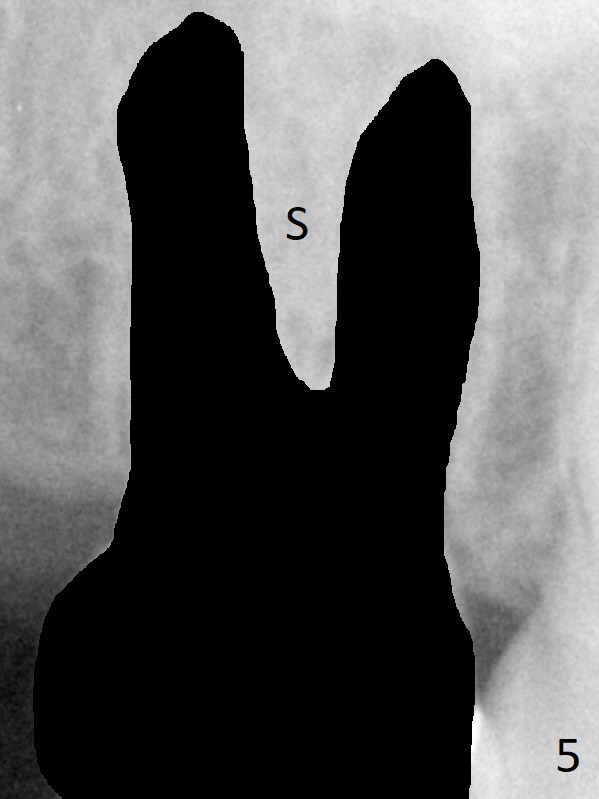

A 58-year-old woman has had RCT done at #2 for several years. The roots are trifurcated with sufficient bone height (Fig.1-3). Recently the tooth becomes symptomatic with formation of a distal fistula (Fig.4). After extraction, the septum (Fig.5 S) may be wide enough for initial drill (Fig.6). If not, resection the thin part of the septum (Fig.7 red line, with small or medium Rongeur) and use the initial drill (Fig.8). Anyway, take PA immediately to avoid sinus membrane perforation. If possible, adopt single drill technique.